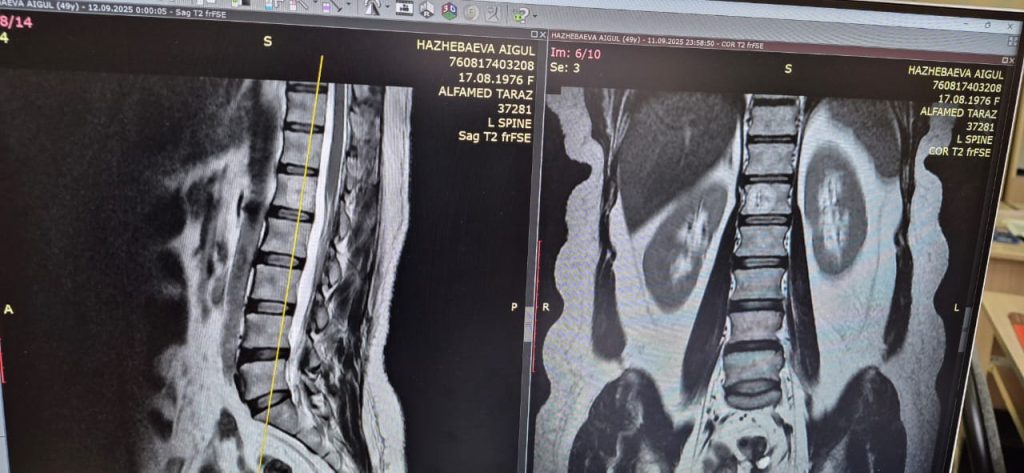

Омыртқа гемангиомасы — бұл омыртқа денесінің ішінде пайда болатын қан тамырлы «түзіліс». Көп жағдайда ол ешқандай белгі бермейді және жиі МРТ кезінде кездейсоқ табылады. Гемангиома халықтың шамамен әр оныншы адамынан анықталады. Әдетте қауіпсіз болғанымен, кей жағдайларда ол үлкейіп, омыртқа құрылымын әлсіретіп, уақыт өте келе белдің ауыруын, аяқтардағы ұю мен әлсіздікті, жүйке түбірлерінің немесе жұлынның қысылуын тудыруы мүмкін. Емделмеген жағдайда омыртқа денесінің компрессиялық сынуына дейін апарып, адамның жағдайын күрт нашарлатуы мүмкін.

Бүгінде гемангиоманы емдеудің тиімді және қауіпсіз әдістерінің бірі — перкутандық вертебропластика. Бұл — теріге кішкентай тілік арқылы жасалатын кіші инвазивті процедура. Операция кезінде әлсіреген омыртқа денесіне арнайы медициналық цемент енгізіледі. Ол омыртқаны бекітіп, гемангиоманың өсуін тоқтатады және ауырсынуды жылдам басады. Процедура шамамен 20–30 минутқа созылады, жалпы жансыздандыру жасалады, ал науқас бірнеше сағаттан кейін-ақ өздігінен жүріп тұра алады.